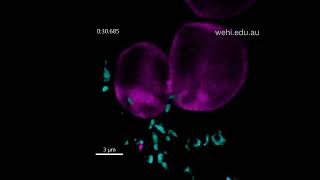

Malaria parasite invading red blood cell Malaria parasites blocked from invading red blood cells

Malaria parasites blocked from invading red blood cells 3D visualisation shows how inhibitor WM382 blocks malaria parasites from invading red blood cells

Malaria parasite invading red blood cell Malaria parasites blocked from invading red blood cells

Malaria parasites blocked from invading red blood cells 3D visualisation shows how inhibitor WM382 blocks malaria parasites from invading red blood cells